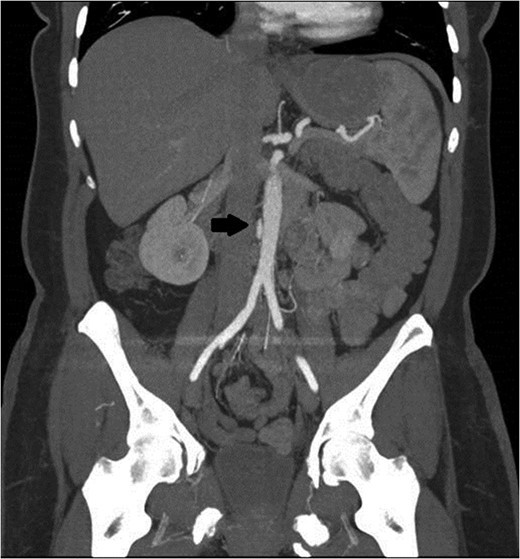

A 47-year-old woman with a history of hypertension and smoking was involved in a high-speed motor vehicle accident and presented to the emergency department with back pain. Computed tomographic (CT) scans were obtained of her abdomen and pelvis. On a single image from the abdominal scan, what appeared to be either an intimal flap or a small amount of contrast extravasation outside of the infrarenal aorta could be seen. Her care providers had differing opinions as to what was being seen on the image. Since the abnormality was only seen on a single image, the exact etiology could not be delineated (Fig. 1). The patient was observed in the hospital overnight, had minimal complaints the next day, and was discharged on aspirin.

Initial CT scan shows enhancing vascular abnormality on the right side of the aorta, shown by the black arrow.